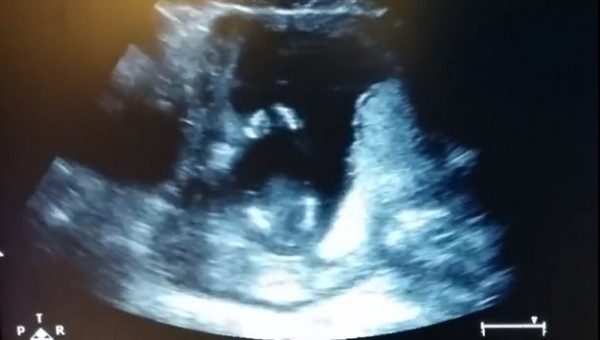

فيديو: جنين "يصفق" داخل رحم أمه

حصد فيديو لجنين يصفق داخل رحم أمه أكثر من مليوني مشاهدة على موقع يوتيوب.

وأثار الفيديو ضجة على مواقع التواصل الاجتماعي، إذ ظهر الجنين يصفق على أنغام الأغنية الإنجليزية "إذا كنت سعيدا صفق بيديك"، والتي كان والده يغنيها في إحدى جلسات التصوير بالأمواج فوق الصوتية.

ونقلت صحيفة مترو البريطانية، عن جين كاردينال والدة الطفل، قولها "إن الفيديو حقيقي، وإن طفلها صفق بالفعل، ولكن ليس على أنغام الأغنية".

وأضافت كاردينال "قام الطبيب بإعادة شريط التسجيل، وبدأ والده في الغناء بشكل متزامن مع تصفيقه، لنحصل على هذا الفيديو المدهش".